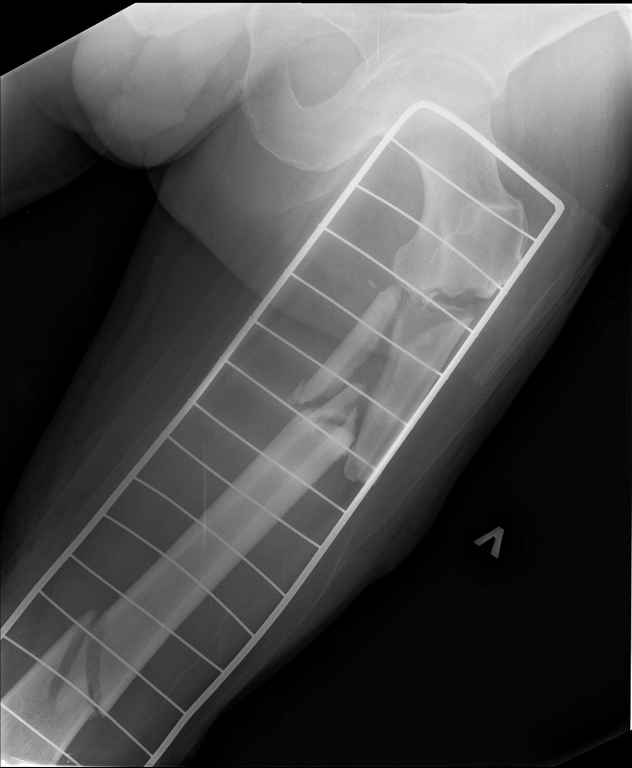

Неделю назад поступил пациент после ДТП. В тяжелом

состоянии. Ds: ТСТ. ЗЧМТ. СГМ. ЗТГК. О/фрагментарный перелом левого бедра. З/оскольчатый

перелом с\3 левого плеча. Перелом левого локтевого отростка. З/перелом наружного мыщелка

б/берцовой кости в/3 м/берцовой кости левой голени. при поступлении, ПХО раны левого бедра(

рана 1х1см по наружной поверхности бедра в с/3) налажено скелетное вытяжение , и гипсовая

лонгета на левую в/конечность.Находился в реанимации.

17.02.11был прооперирован: БИОС левого плеча, о/синтез левого

локтевого отростка по Веберу, БИОС левого бедра( длинная

версия Fi-Can Sanatmetal диаметр 10мм), мыщелок голени трогать не стали.при остеосинтезе

бедра возникли трудности при закрытй репозиции перелома в н/3, в связи с чем решили открыться

внизу , отрепонировали без особого труда и выполнили блокирование во фронтальной плоскости

3-мя винтами + 1 винт спереди гвоздя( промазал). Убрал костодержатель, все нормально,

контроль ЭОПом стояние отломков нормальное, зашились. На контрольной R-мме на утро

выявлено вторичное смещение дистального отломка. Левая нога по сравнению со здоровой

удлиннена до 2,5см( это за счет вальгусной установки гвоздя в проксимальном отделе, боялся

свалиться на варус).